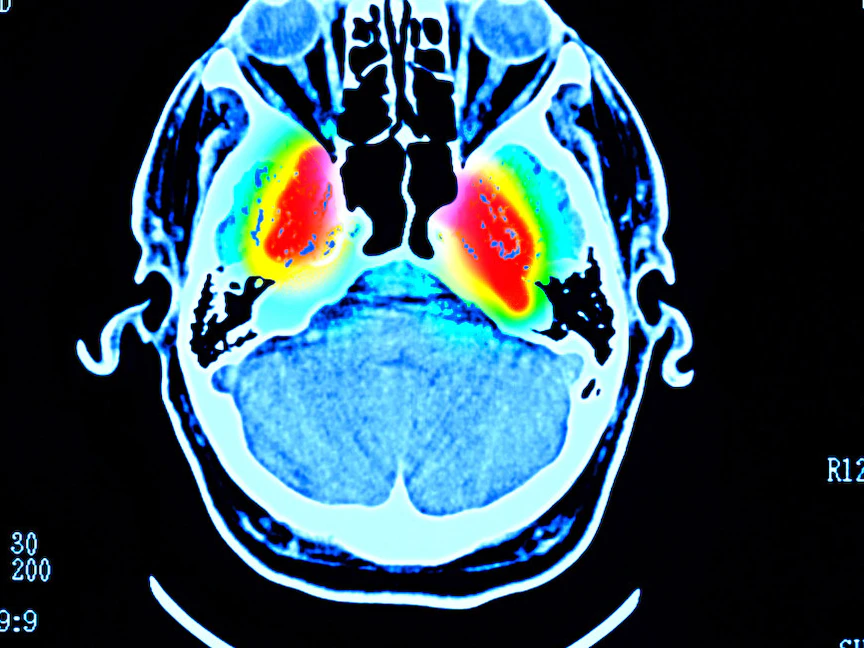

ويسبب الضمور الجهازي المتعدد تلف وانكماش (ضمور) أجزاء من الدماغ مثل المخيخ والعقد القاعدية وجذع الدماغ، والتي تؤثر على وظائف الجسم الداخلية والتحكم الحركي.